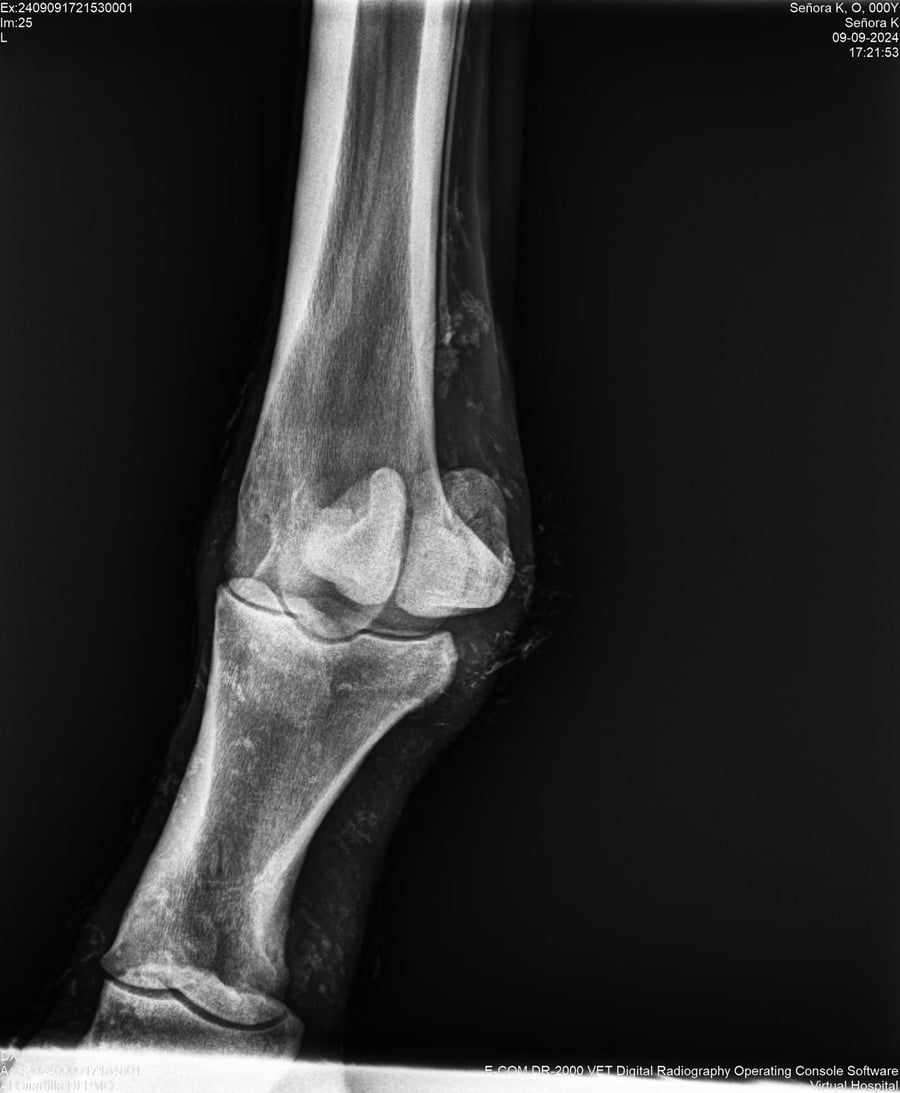

LOTE 44, SEÑORA K

Identificador: #291147-

Generacion 2022